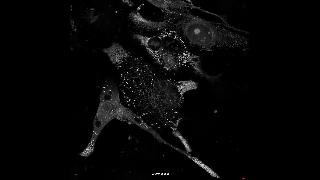

연구팀은 캐리옵토시스라고 이름붙인 세포 사멸 과정을 세계 최초로 영상 촬영하고 분자들의 반응과 원리를 규명했다.

캐리옵토시스의 기본 개념은 2018년 영국에서 처음 제안됐지만 지금까지 핵막이 손상되어 세포가 사멸하는 과정은 정확히 밝혀지지 않았다. 연구팀은 캐리옵토시스라고 이름붙인 세포 사멸 과정을 세계 최초로 영상 촬영하고 분자들의 반응과 원리를 규명했다.